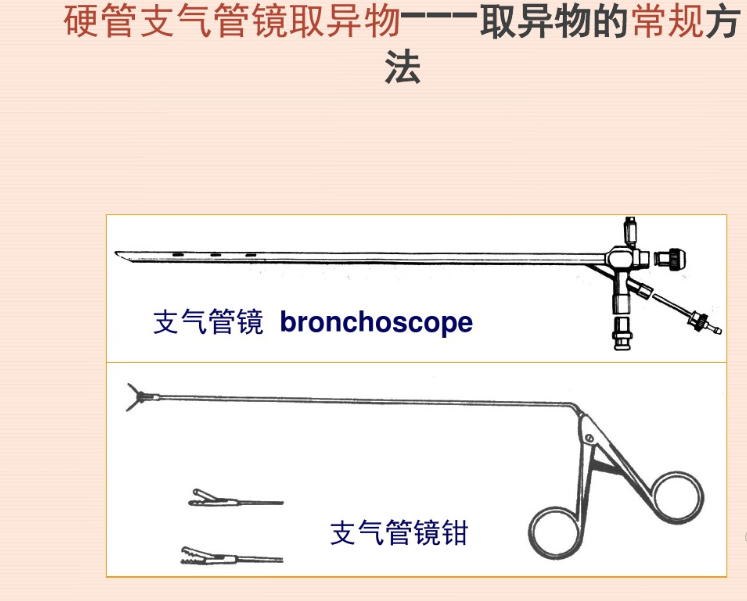

考虑到白虾质地较软,异物钳钳夹过程中可能导致虾头与身体分离、碎裂,导致取出困难,介入团队在商议后决定给患者进行冷冻取异物术。

及时诊断、尽早取出

后话:瑞安市人民医院呼吸科目前已经拥有非常成熟的内镜下各种异物取出技术,包括包括内镜下异物钳、异物网兜、冷冻等技术,每年均有数十例气管、支气管异物取出的案例,取出的异物多种多样,有辣椒皮、鸡骨头、豆类等等,异物留置在气道内时间从几小时至十余年不等。异物呛入会导致窒息、肺脓肿、支气管扩张、大咯血等危及生命的并发症,希望广大市民朋友们在走亲访友时注意饮食安全,避免进食呛咳,万一有异物被呛入的情况,请及时到医院就诊!